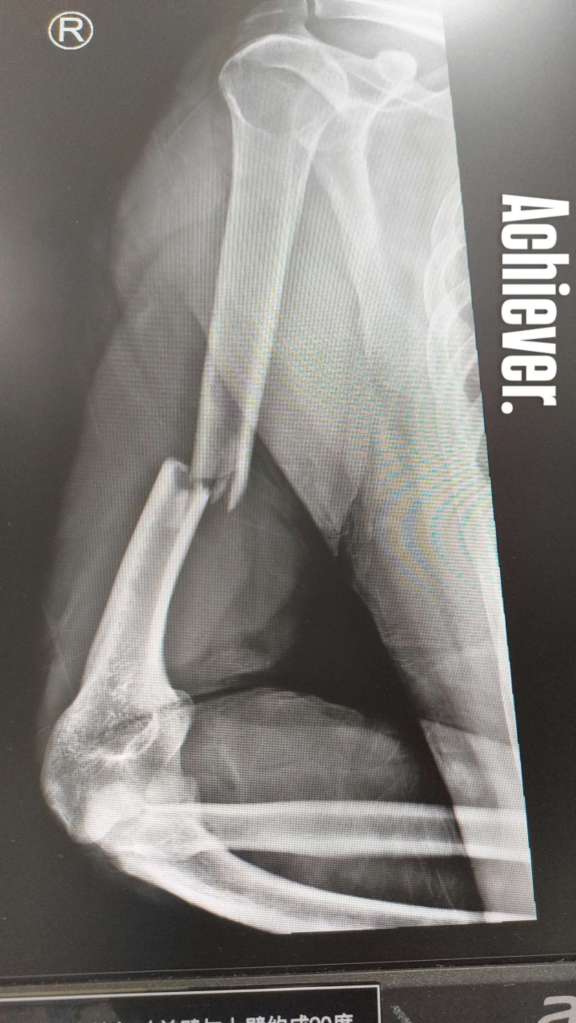

First, I’d just like to point out that whenever I set my mind to doing something, I do it to the absolute best of my ability. See X-ray for for one fine example of my work:

If this looks painful, it was. But probably not in the way you think it was painful. When I slipped, banana-peel style, on a muddy ramp and fell on my ass, I unfortunately caught myself with my right arm at a weird angle (I was wearing my backpack, too), causing what I think is called a “spiral fracture.” I immediately knew my arm was broken and, at that moment, I felt no pain, just the sickening discomfort of flaccidness from mid-humerus down. When you break your arm like this, you lose the structural integrity of the limb, which means your arm is only held together by soft tissue—bicep and my tricep—any force directed against holding the arm together is transferred from the bone to the ligaments and muscle tissue, which is a very strange, unsettling feeling indeed.

Unfortunately, the extremely thorough nurses who attended to me immediately also insisted I get an X-ray, sign some forms (mind you: I broke my right arm, aka my writing arm), pay them 5,000 yuan, and recite various identification numbers, etc. At the time, though I do not remember feeling pain, I do remember having significant difficulty remembering numbers I have memorized by heart (like my passport number, my phone number). But we got through the bureaucracy. When they printed the X-ray (above), everyone was sufficiently convinced as I was that immediate drugs were in order.

During these days I did a lot of gently shuffling around the hospital, making myself a nuisance to the staff out of boredom. The nurses at HKU-SZ Hospital worked with clocklike efficency: take your pill, time for ice, after lunch take this pill. When I woke up on Sunday, they walked me down the hall to get more X-rays.